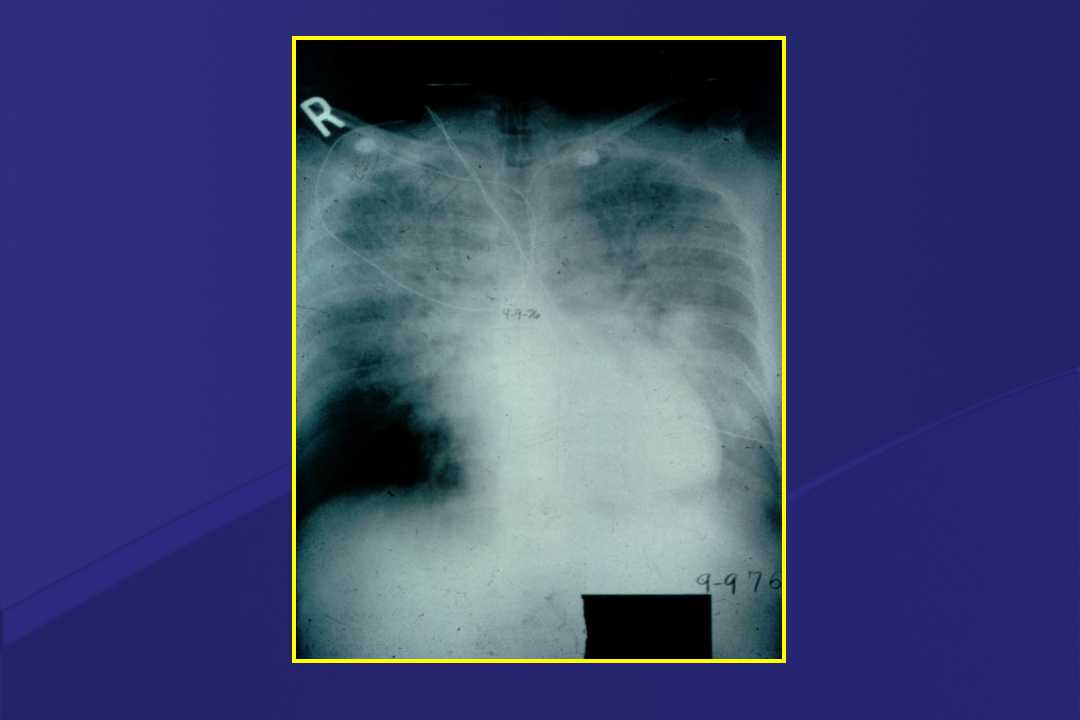

血液疾病患者肺部并发症影像学表现